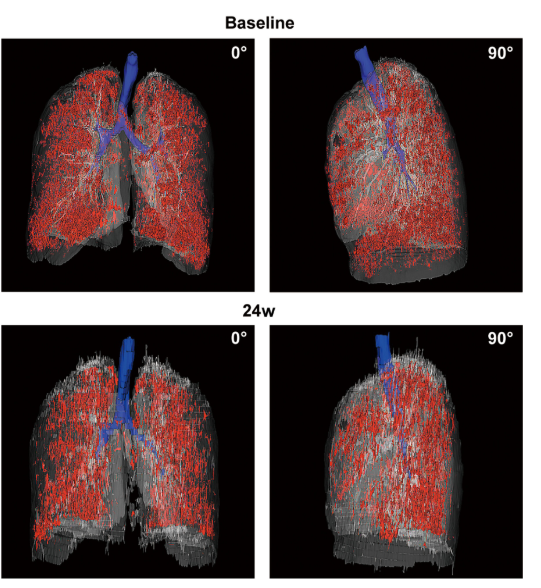

影像學(xué)檢查:對(duì)于患者 #2902,定量分析顯示基線時(shí)總體肺氣腫面積比為 12.75%,移植后 24 周降至 10.02%。在患者 #8009 中,肺氣腫面積比值從基線的 10.85% 下降到移植后 12 周的 9.08%。CT 圖像的三維可視化顯示,肺氣腫的減輕在下葉比在上葉更明顯。